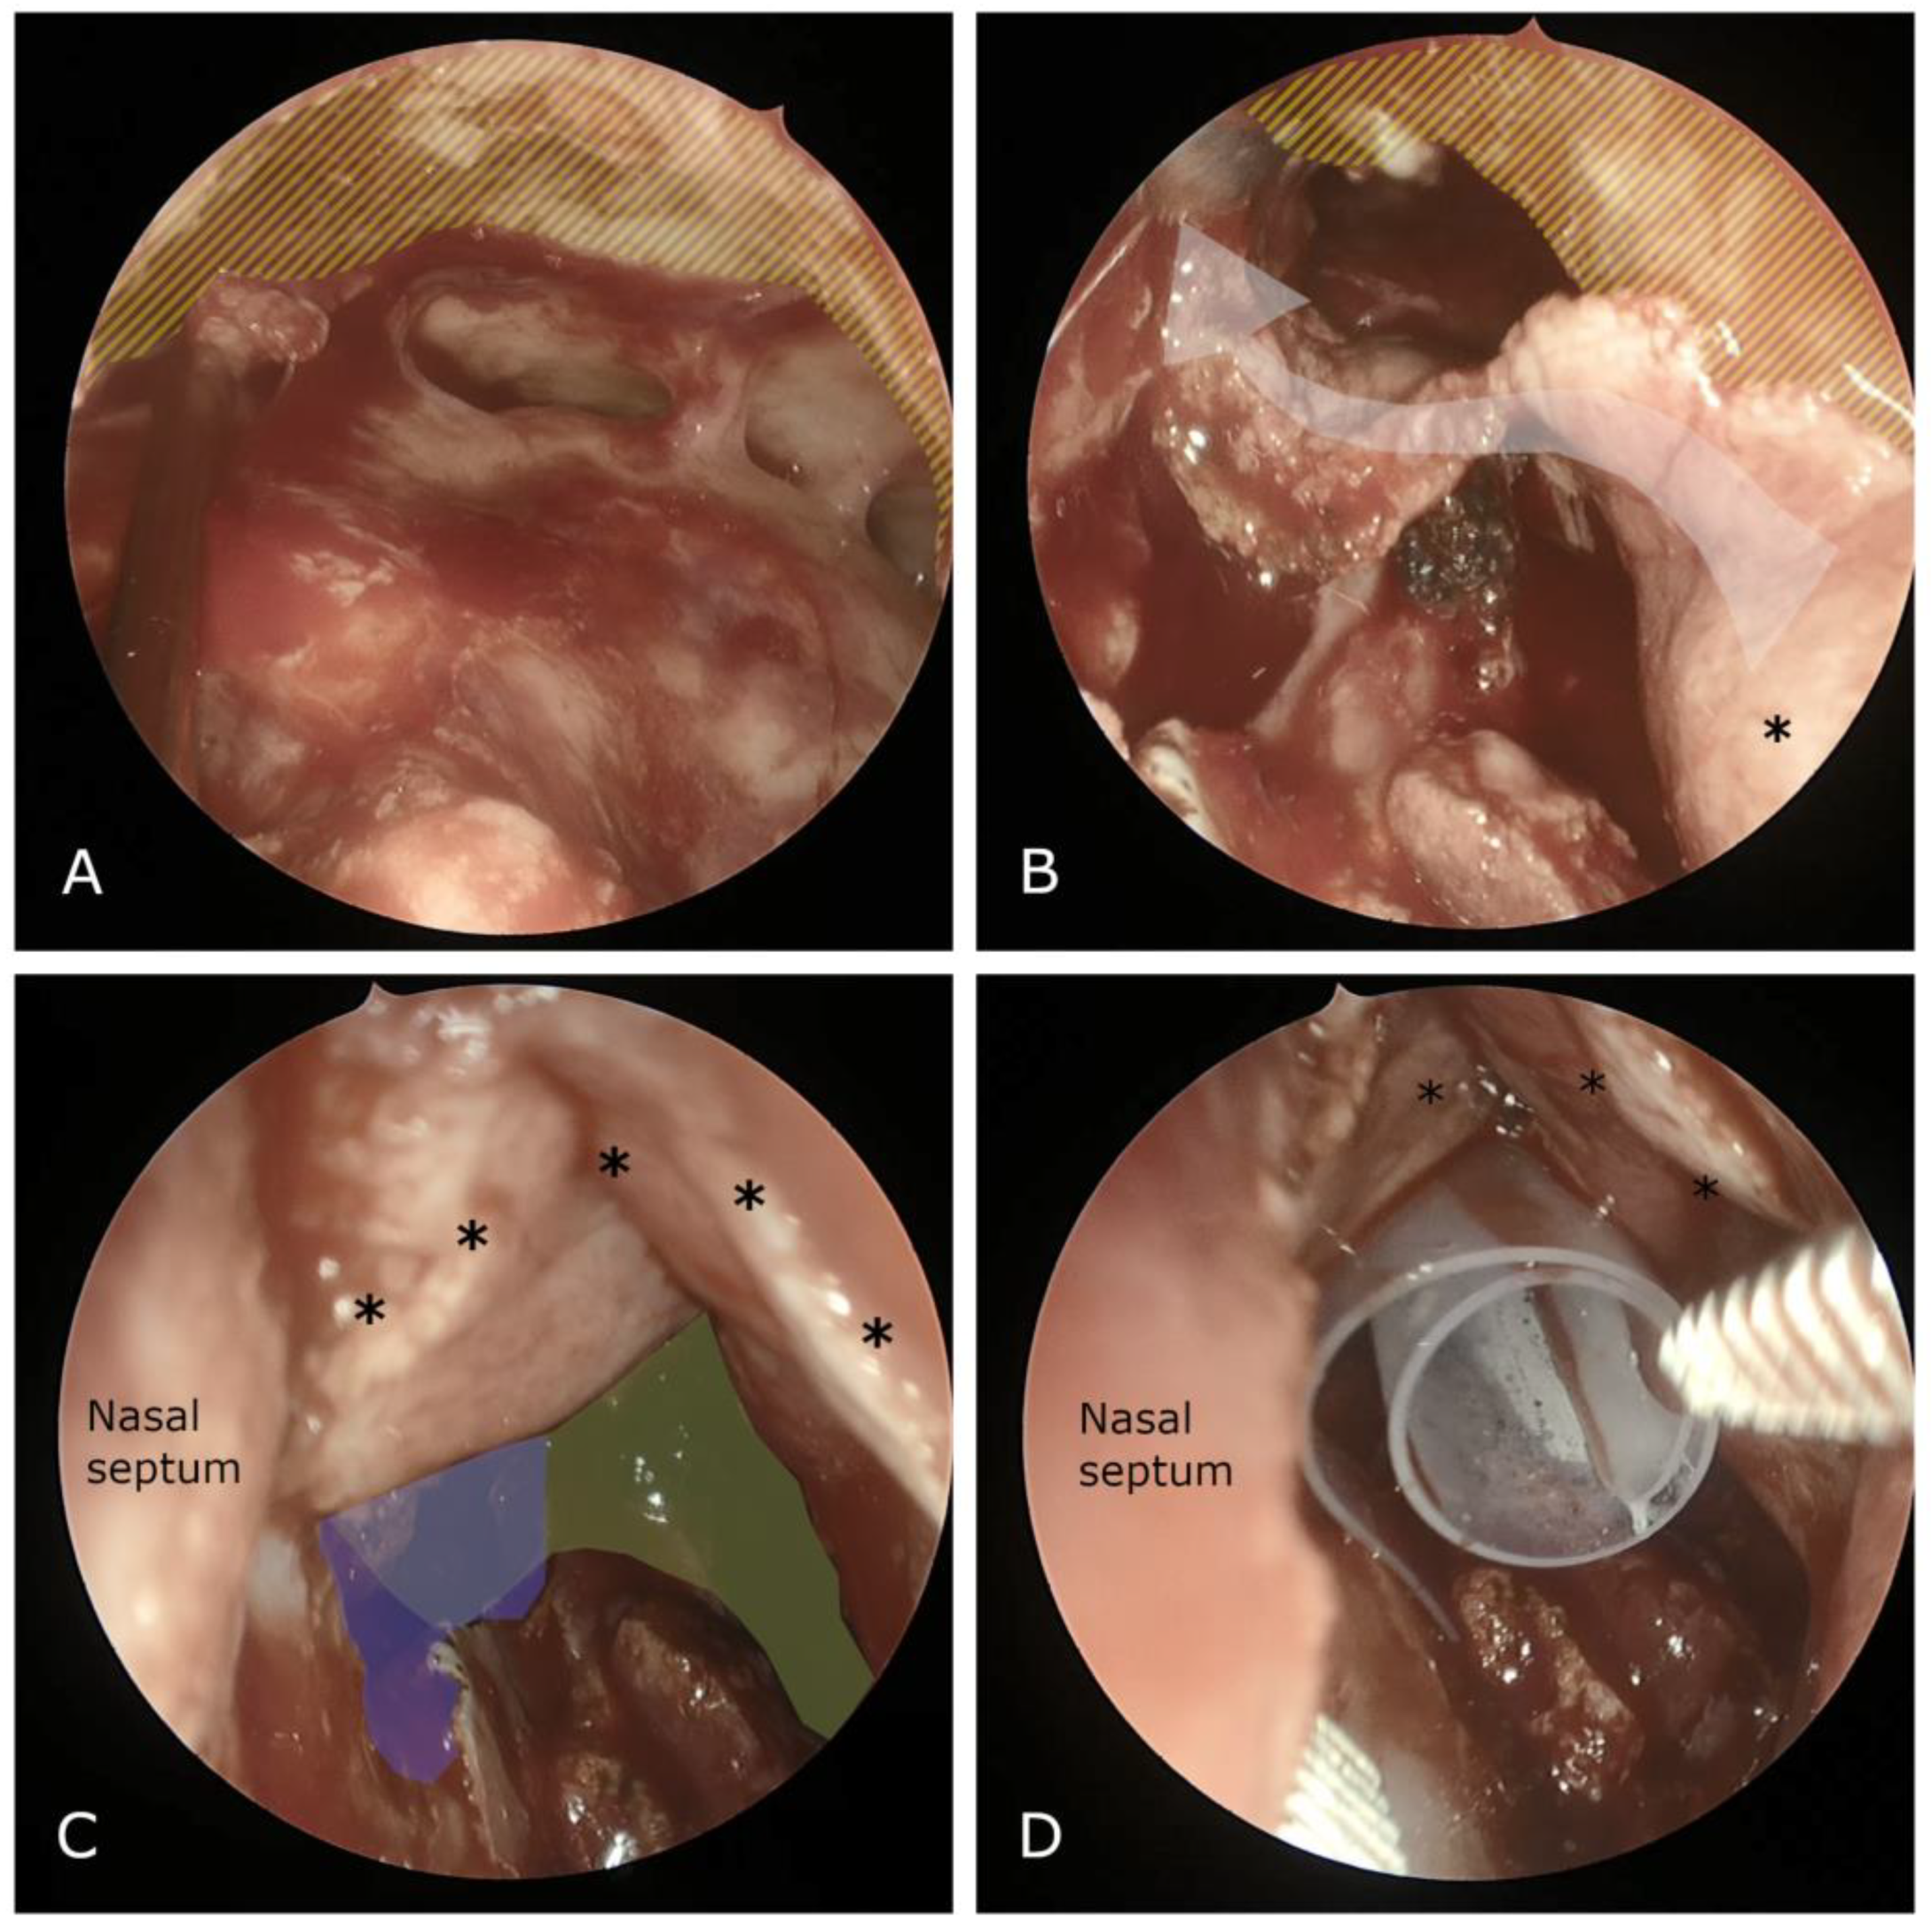

Figure 1. (A) Intraoperative perspective depicting the unified frontal sinuses subsequent to a Draf III procedure, prior to flap placement. Note the extensive bone exposure following the drill-out; (B) the laterally based flap (left side), mobilized for coverage of the exposed bone (asterisk denotes base of the flap); (C) conclusive view displaying the flap in situ (asterisks denote flap placement, green indicates neo-ostium, purple represents septal window); and (D) a 0.25 mm silastic sheet utilized to secure the flap (asterisks) postoperatively for 4–6 weeks.

In approximately two-thirds of the patients we used the lateral-to-medial (inside-out) approach, while in oncological cases involving benign and malignant sinonasal tumors we used the medial-to-lateral approach. Mucosal flaps and free grafts were utilized in 36% of cases, with the exception of malignant cases where they were never employed. Specifically, free grafts were utilized in 30.8% of cases with flaps/grafts, laterally based flaps in 61.5%, and middle turbinate septal flaps in 7.7% (Scheme 2, Figure 1).